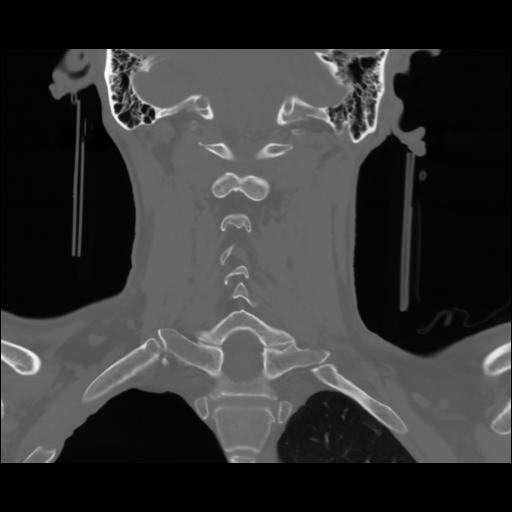

13 P.BLANDAS,,Coronal,2.000,P.BLANDAS,Coronal,